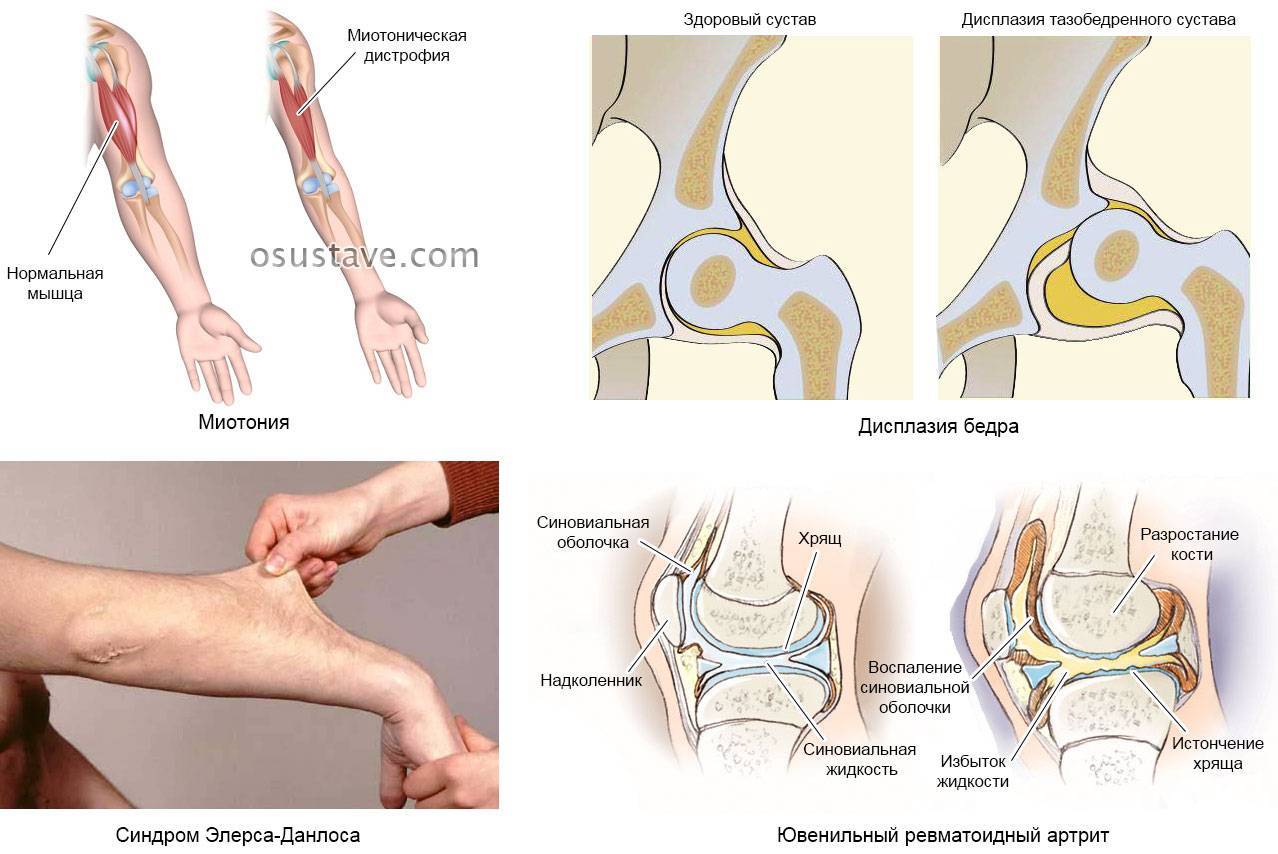

Дисплазия. Основные причины этой патологии – изменение структуры коллагена, вызванное генетическими причинами, и нехватка компонентов, из которых строится соединительная ткань. Заболевание проявляется частыми вывихами, искривлением позвоночника, пролапсом митрального клапана, близорукостью, плоскостопием. Хруст в суставах также может быть одним из симптомов.

Нехватка внутрисуставной жидкости. Еще одна патология, которая обусловлена наследственными факторами. Помимо щелчков, ребенка могут беспокоить снижение подвижности суставов и боль при движении.

- Дисплазия соединительной ткани (ДСТ). Возникает внутриутробно, при формировании генетического материала плода. Развитие дисплазии связано со структурным изменением коллагена и недостатком компонентов соединительной ткани. Как результат, у детей отмечается гипермобильность («слабость») в суставах, проявляющаяся болезненностью и частыми вывихами. Треск и скрипение в суставах обусловлены растяжением связок и «разбалтыванием» суставов, вследствие чего происходит соприкасание хрящевых поверхностей. Среди других симптомов ДСТ — низкая масса тела, деформации позвоночника, плоскостопие, пролапс митрального клапана и другие.

- Артрит (воспаление одного или нескольких суставов). Изменения в хрящевой ткани при артритах проявляется трещинами, расслоением, истончением, что приводит к появлению скрипения при движениях в суставе. Кроме того, хруст и треск связаны с изменениями в костной ткани — появлением уплотнений, шипов, наростов.

- дисплазия тазобедренного сустава, которая часто встречается у детей. Вывих бедра чаще всего диагностируют у у младенцев, но он может возникнуть и во время подросткового возраста при формировании опорно-двигательного аппарата;